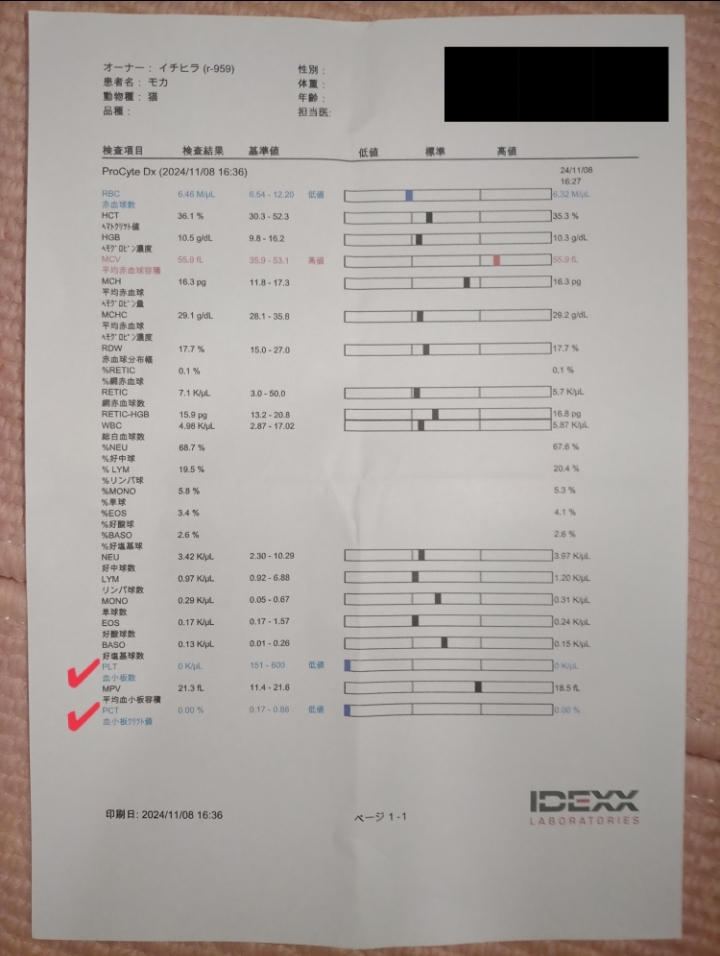

2024年11月5日🏥

いつものように検査をしていたら、

左側の腎臓だけ形がボコボコに…💦

更に、ここ2年ほど落ち着いていた血小板減少症もまさかのタイミングで再発…💦

数値がまたゼロに💦💦

今回、何が問題だったかというと、血小板がゼロだと血を止めることができず、本来であれば腎臓に異変があった時点で針生検をする必要があったのですが…できず💦

リンパ腫再燃疑いがあっても、まずは血小板減少症の治療を始めなければならずで、順調に減薬していたステロイドをまた大容量に増やし、一旦数値が上がるまで様子を見ることに︎😖՞ ՞

一度数値が安定したものの、また下がってしまった為、今は免疫抑制剤(アトピカ)も併用しながら経過観察中なのですが、

ステロイドが第一選択にはなるのですが、長期服用や大容量では様々な副作用がある為難しく、モカはステロイド減薬の途中でまた数値が下がってしまった為、免疫抑制剤(アトピカ)の併用しか道がなく、今は様子を見ながら進めています😭